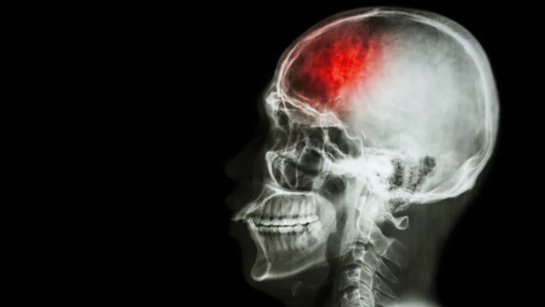

Исследователи из Университета Джорджии разработали новое лечение повреждений после инсультов. Они прибегли к помощи стволовых клеток.

При тестировании на животны было обнаружено, что метод уменьшает повреждение головного и помогает

По данным CDC, инсульты затрагивают почти 800 тысяч человек каждый год в США, и из них около 140 тысяч – умирают.

Оставшиеся в живых обычно сталкиваются с длительным периодом реабилитации, и в тяжелых случаях может наблюдаться постоянное повреждение головного